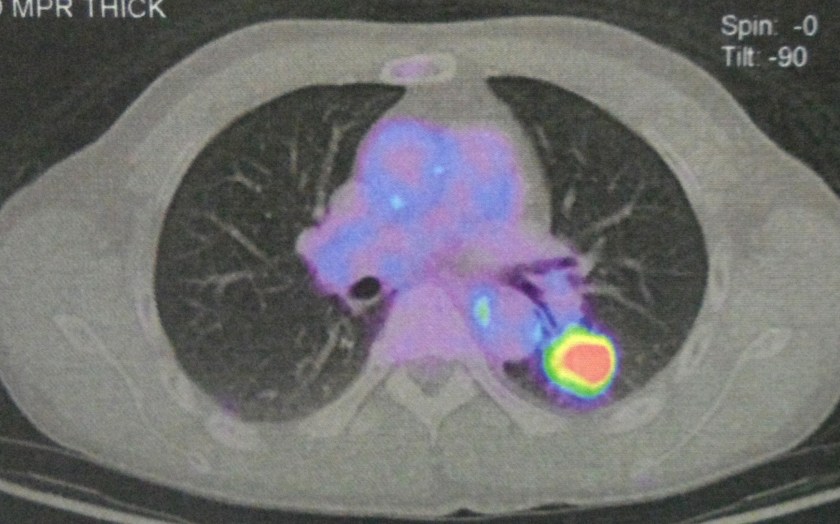

PET scan on 10 August 2017 indicated:

- FDG avid primary at the mid oesophagus.

- Intense FDG uptake in the left upper lobe lung nodule — suspicious of metastasis.

- Small focal FDG avid lesion at L3 vertebra — suspicious of small volume metastasis.

- No conclusive FDG avid lesion demonstrated elsewhere.

Study the three pictures below and compare them with the PET scan done on 10 August 2017 (above). You don’t need to be a doctor to know that PK is not getter better. He is getting worse and the cancer has spread more widely.

The PET scan report of 11 April 2018 stated the following:

- New development of large reticulonodular changes at the left upper lobe, probably related to post-radiation inflammation.

- New FDG avid mediastinal nodes, probably reactive nodes from inflammation.